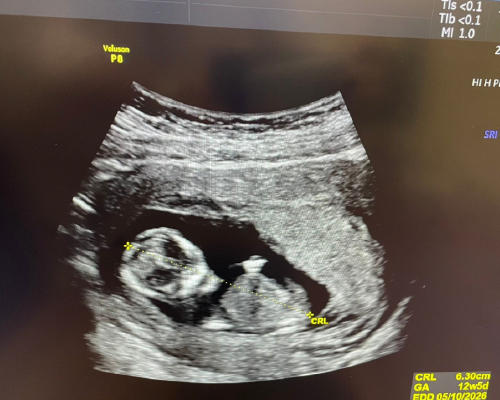

今天胎兒心跳及活動力都很好💖

非侵入性NIPT染色體基因檢測是低風險